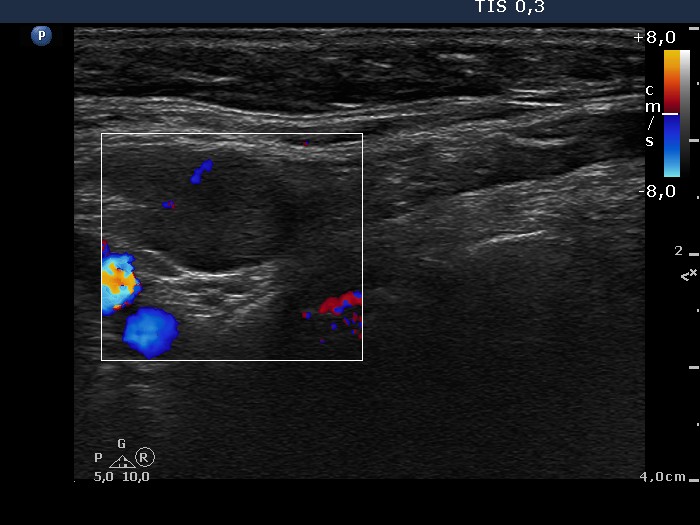

Ultrasonography. The thyroid was composed of multiple nodules with different echogenicities. There was a small hypoechogenic lesion above the right lobe.

Cytology was performed from the lesion above the thyroid and resulted in benign colloid goiter.

Histopathology disclosed benign hyperplastic nodules even in the case of the lesion above the right lobe which was located outside the thyroid.